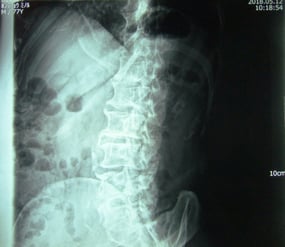

レントゲン検査の結果を見て、整形の先生の見解は「骨が変形していて間も狭くなっているので歩くのは控えて」ということでした。

私は、疑問に感じたので後日、レントゲン画像を見せてもらいに病院に足を運んだ。

確かに多少の変形はあるものの、年相応の退行性の変形であり、関節の間も比較的しっかりしていると判断し、父には気にしなくて良いので、今まで通りにウオーキングの継続を勧めた。